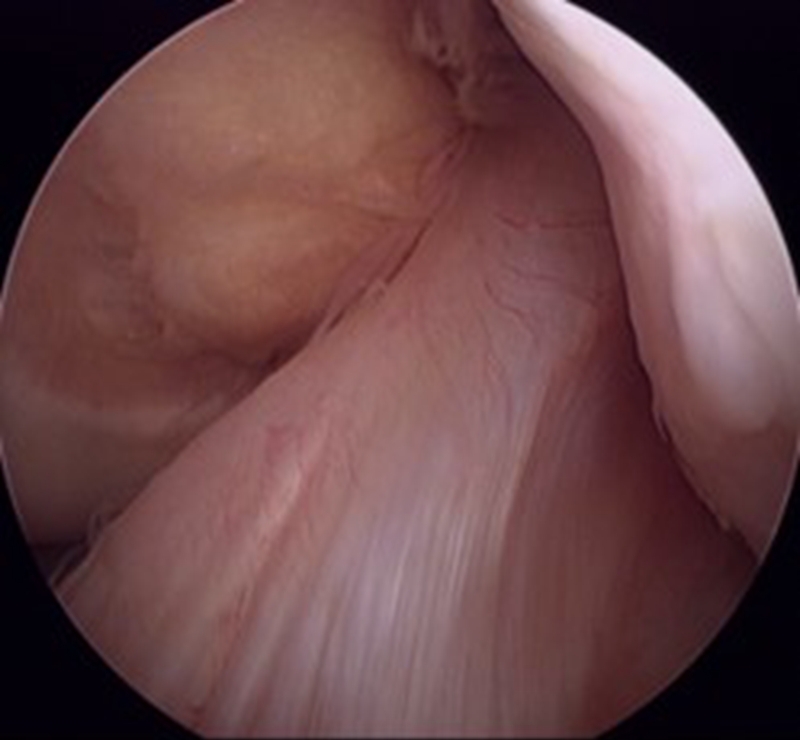

(2)腘绳肌腱:是目前临床最常用的自体移植物。重建后韧带的强度不逊于自体骨髌腱骨,半腱肌腱与股薄肌腱单根并用,初始强度平均可达2736N,大于正常ACL的断裂强度,接近髌腱1/3部的强度,而且局部创伤小,取材方便。